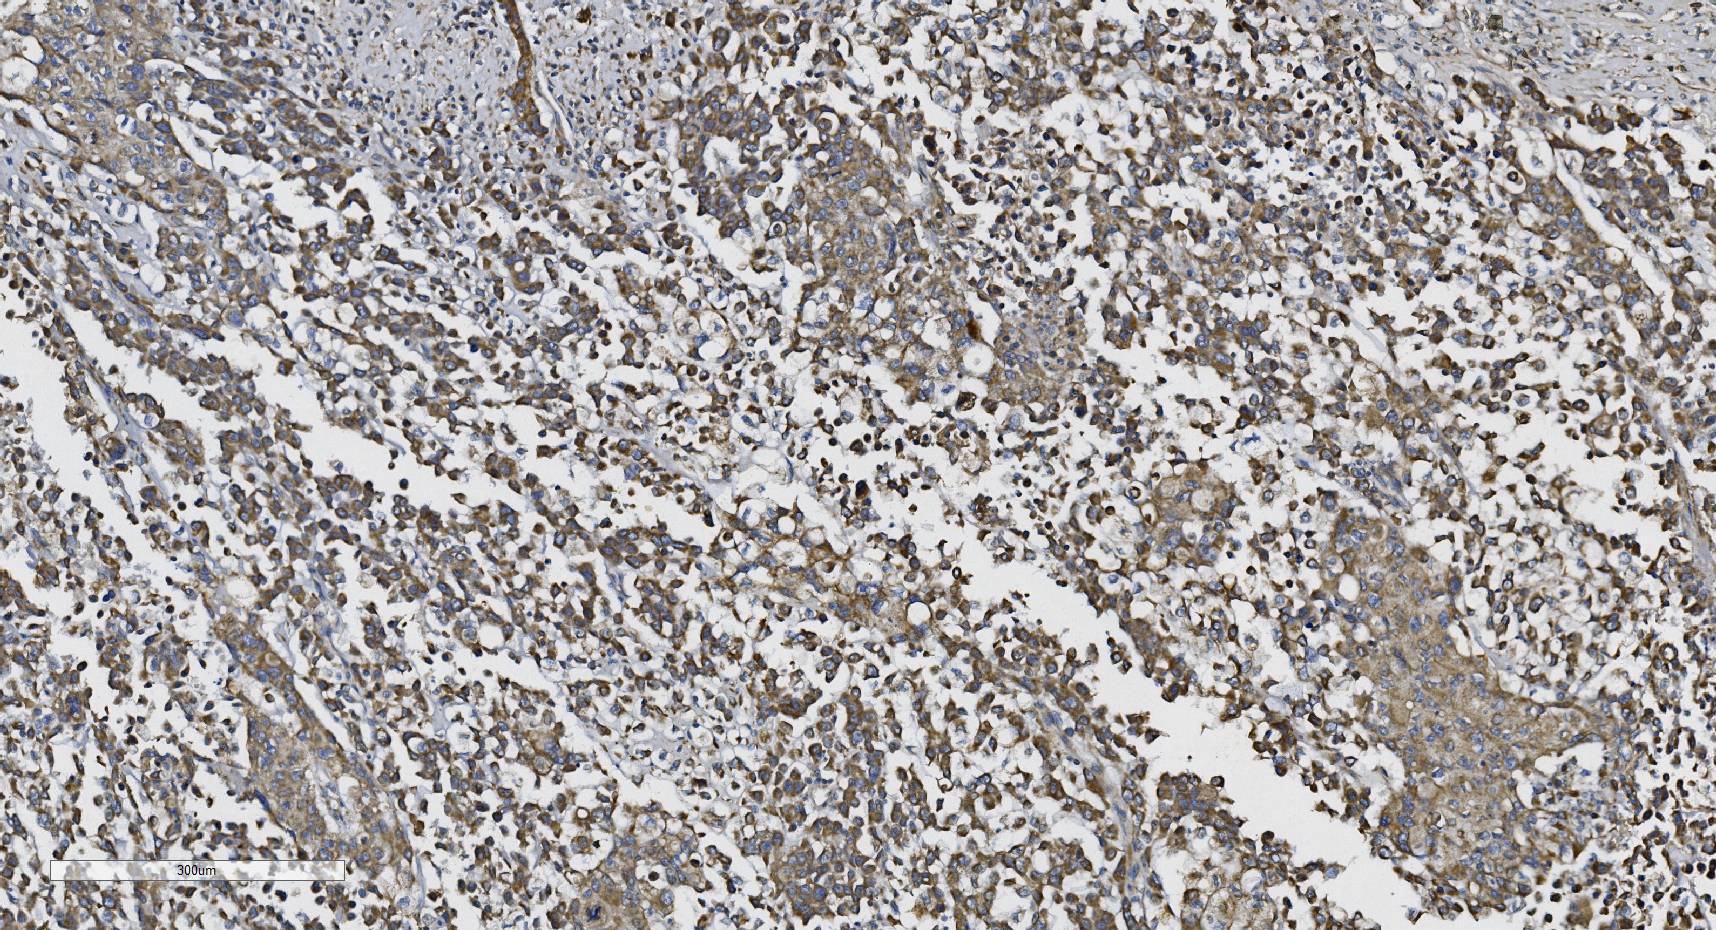

IHC analysis of N-Cadherin/CDH2 using anti-N-Cadherin/CDH2 antibody (A01577-3).

N-Cadherin/CDH2 was detected in a paraffin-embedded section of human lung cancer tissue. Biotinylated goat anti-rabbit IgG was used as secondary antibody. The tissue section was incubated with rabbit anti-N-Cadherin/CDH2 Antibody (A01577-3) at a dilution of 1:200 and developed using Strepavidin-Biotin-Complex (SABC) (Catalog # SA1022) with DAB (Catalog # AR1027) as the chromogen.